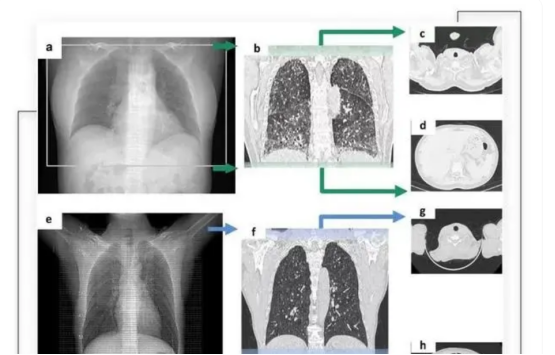

AI医学影像分析,则是利用机器学习、计算机视觉等技术,对医学影像数据进行自动化分析和诊断,并根据大量的定量特征,如形态、纹理、灰度、强度等,与基因、临床等其他数据进行关联分析,发现疾病的生物标志物和预后因素。

通过搭载了智能算法的CT摄像头,将深度学习卷积神经网络与典型的模式识别算法创新地结合在一起,从而精准识别CT扫描范围。

其主要技术,是通过深度学习及卷积神经网络模型,模仿人类认知过程,让AI模型自动挖掘医学图像中的规律。